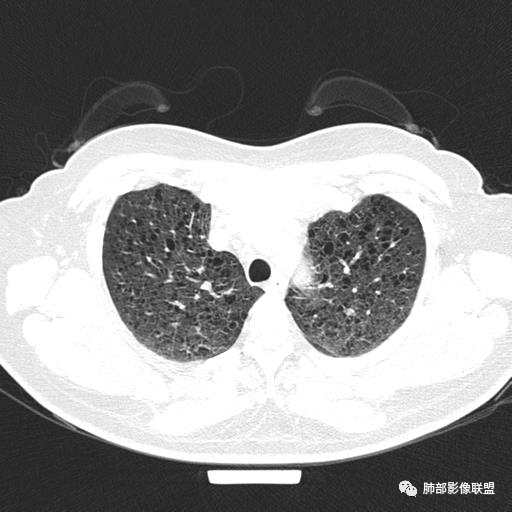

女,46,活动性气喘1年。苯吸入史半年。胸部CT:两肺弥漫囊腔,上至肺尖,下至肋膈角,形态类似小囊腔。考虑:LAM,鉴别LIP,BHD,PLCH等。

双肺弥漫大小不一薄壁含气囊腔,囊间肺组织正常,正常肺背景,肺尖肺底受累;青年女性,气喘,支持LAM

CT表现:双肺弥漫大小不等的薄壁囊腔,囊壁<2mm,外形规则,血管影多位于囊腔周围,囊腔之间肺组织正常,随着疾病进展到晚期,囊腔变大、增多,不可胜数,囊腔可融合成较大的囊,与肺气肿相似,形成间质性肺纤维化。部分病例可出现结节影。